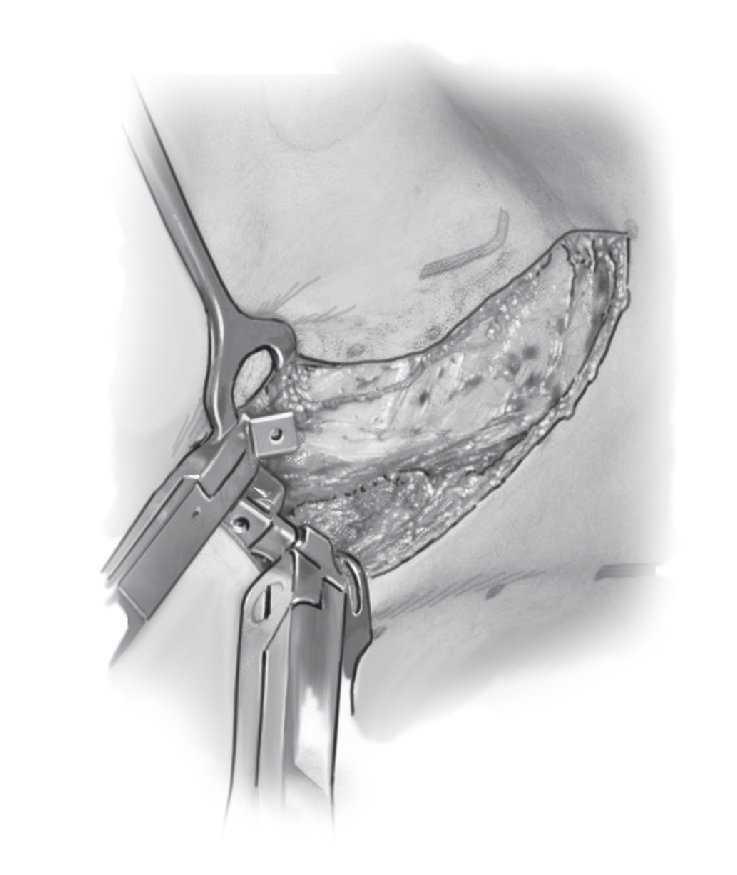

Escoliosis torácicas congénitas con sinostosis costales

Figura 4. Para la toracotomía se practica una incisión arqueada desde el lado dorsolateral. El paciente se coloca en decúbito lateral. Las capas musculares se seccionan secuencialmente hasta exponer las costillas. Debe tenerse cuidado de no preparar la CD y a no ejercer tracción sobre el plexo braquial durante la movilización del hombro. Conviene que los niños sean intervenidos siempre bajo monitorización neurológica.

Figuras 5a y 5b. Exposición de la sinostosis costal (a) y osteotomía de la sinostosis costal con el osteótomo. El sitio de la osteotomía se distrae progresivamente con el separador laminar (b). Debe prestarse atención a desprender las adherencias costales de la pleura con un porta-algodón para que no se produzcan lesiones en la zona del pulmón.